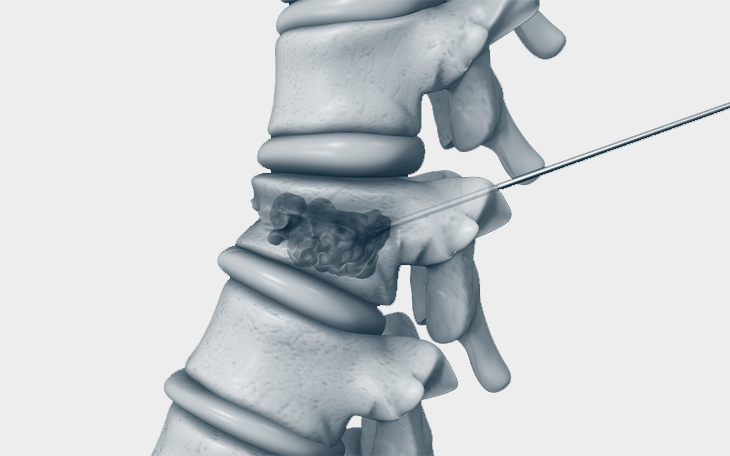

• Wenn konservative Behandlungen nicht ausreichen, können minimal-invasive Eingriffe wie Kyphoplastie erwogen werden. Dabei wird Knochenzement (z. B. PMMA) über eine kleine Hautöffnung in den Wirbel eingespritzt. Das Verfahren ist risikoarm und kann schnell zur Schmerzlinderung führen.

Konservativ: Ein Korsett wird in der Regel für 12 Wochen konsequent getragen.

Operativ: Stabilisierung mit Schrauben-Stäben von hinten, eventuell zusätzlich von vorne.